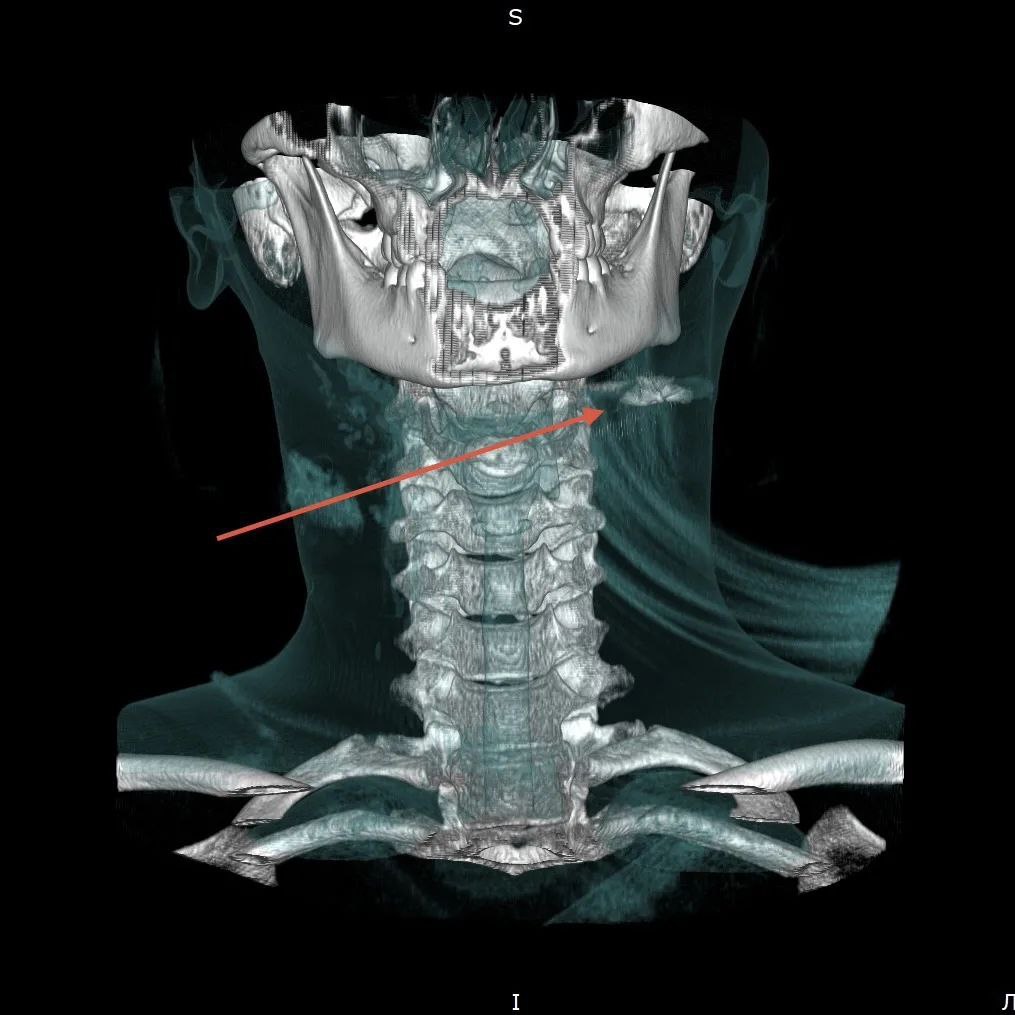

Девочка наткнулась дома на отцовский пневмат и решила пострелять. Один выстрел оказался роковым: пуля попала в область шеи, задела гортань и остановилась рядом с яремной веной. Еще несколько миллиметров и ранение могло стать смертельным.

Пострадавшую сначала увезли в городскую больницу, затем срочно перевезли во Владивосток. После КТ ей провели сложное хирургическое вмешательство. Сейчас угрозы жизни нет, ребенок остается под наблюдением специалистов.